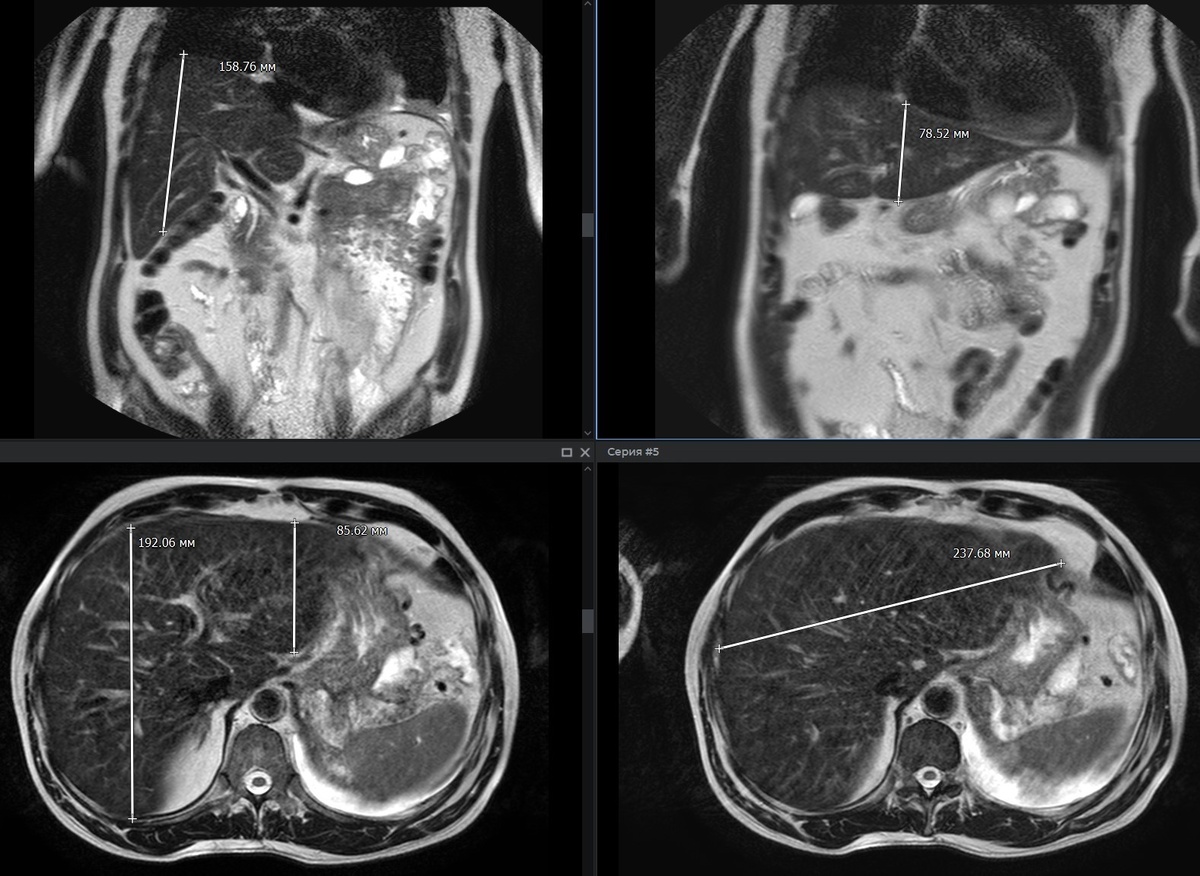

Рис.1: Т2-ВИ корональная и аксиальная плоскость. Печень увеличена: максимальный вертикальный размер правой доли по СКЛ - 15.8 см (норма до 15,0 см), левой доли -7.8 см (норма до 10,0 см), передне-задний размер: правой доли - 19.2 см (норма до 15,0 см), левой доли - 8.5 см (норма 5,0-6,0 см), латеро-латеральный размер печени - 23.7 см (норма 23,0 см). Линейный коэффициент печени - 303 /норма до 256/.